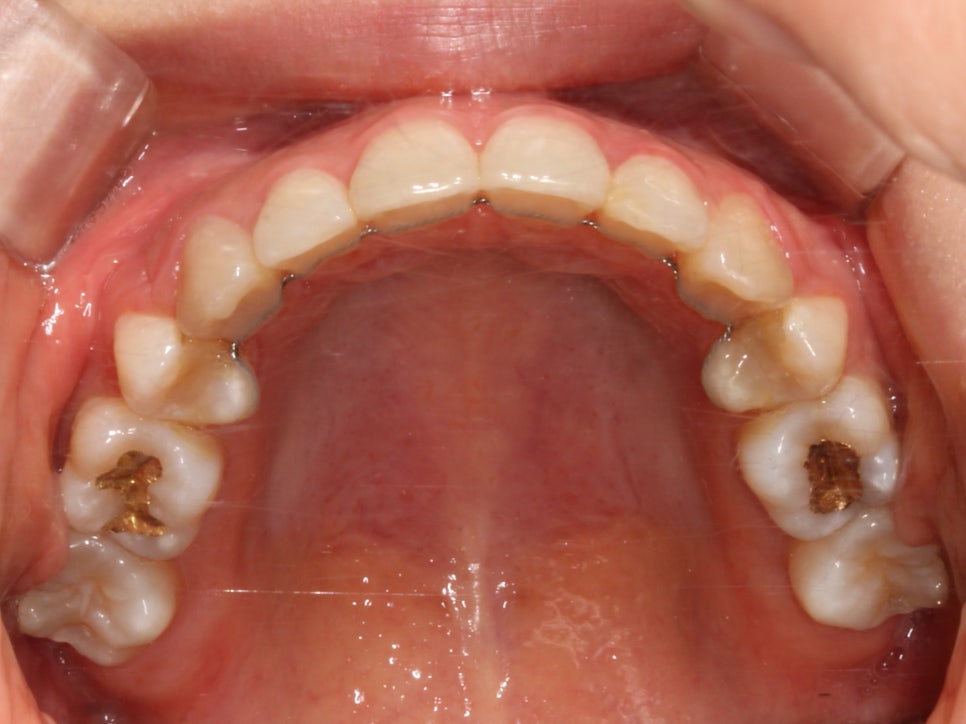

돌출입, 덧니교정 2D교정으로 진행 (전 사진)

돌출입, 덧니치아 2D교정으로 완성! by.투디치과(2D치과)

교정 중 크게 티가 나지 않는 것을 원하셔서

치아 상태를 살피고 적당한 치료방법이 있는지

정밀 진단을 진행했습니다.

상악과 하악의 교합면이 고르지 못하고

원하시는 교정 방향이

장치가 겉으로 드러나지 않기를 희망하셔서

치아 안쪽, 설측으로 교정을 진행하는

2D교정(안보이는 교정장치)로

결정했습니다.